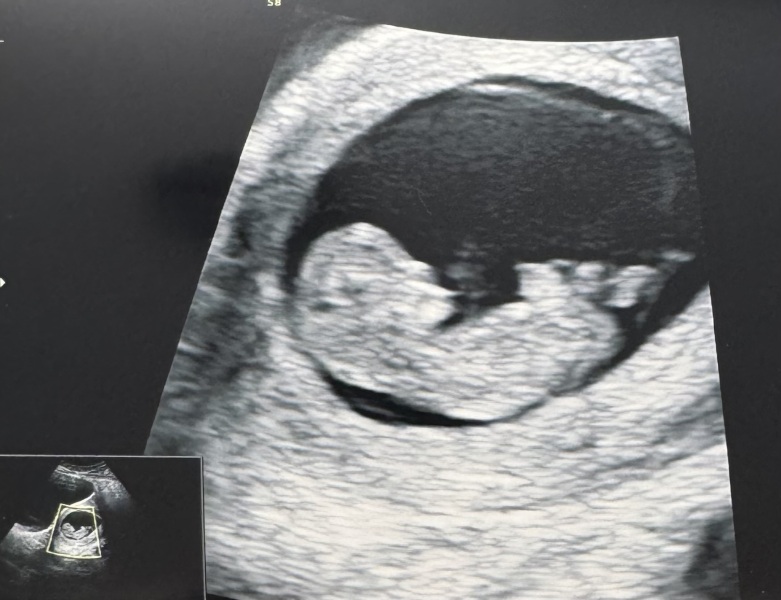

@Riverstardust @Nbaby scan yesterday was amazing. So much growth in 2 weeks. I’m still a week behind from LMP but I think the measurement is correct as I’m sure I ovulated a week late! Measuring 10w1d. Such a clear image. Wriggling around too!